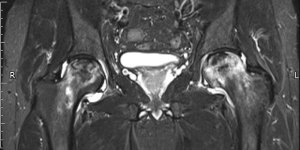

Back Pain | Ankylosing Spondylitis | Cases

Published on Jan 20, 2021

26 ♂ Presented to MSK service with back pain. Gave a 7 year history of back pain (started aged 19) Seen previously in MSK service 5 years ago (aged 21). Had an MRI scan which was normal. Has has physiotherapy in the past. Has been regularly having chiropractic treatment. Reports that his back remains arched when he is lying supine (lordosis [...] Read more